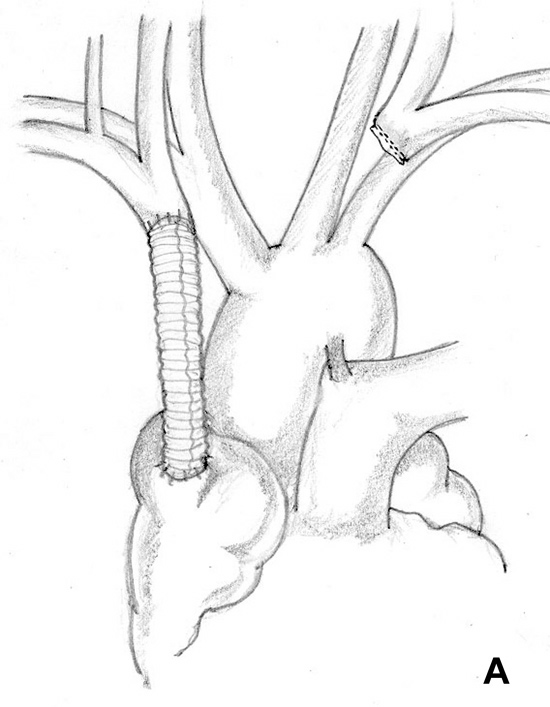

Figure 5A & B. (A) Intraluminal shunt. (B) Extraluminal shunt during reconstruction of the superior vena cava. Surgical strategy and shunting techniques: Every effort should be attempted to reduce clamping time as much as possible, in particular when the SVC system is not completely occluded before the operation. It has been reported that up to 45 to 60 minutes of complete clamping is usually tolerated with the appropriate pharmacological support. For lung cancer resection, the vascular step should be always performed before any other reconstructive procedure of the airway. For mediastinal tumors involving the upper lobes, the dissection should be performed from the left to the right side; the right part of the excision is usually performed after vascular reconstruction, in particular when a lobectomy is required. Intravascular or extravascular shunts (Figure 5) may be used to reduce the effects of vascular clamping during resection and reconstruction of the SVC[4]. However, thrombosis of the shunt may occur; furthermore, these devices occupy space in the operative field making the anastomosis more difficult.

![]() |